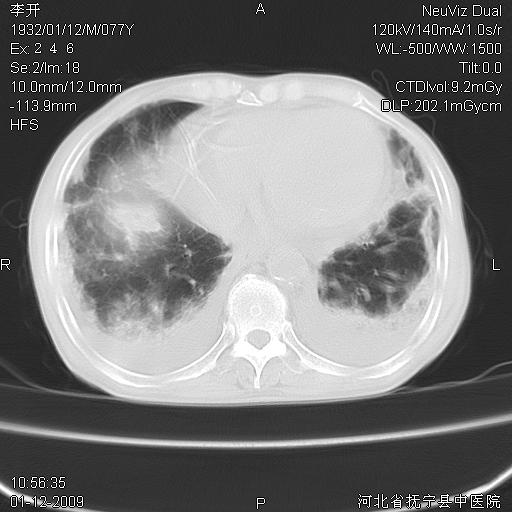

以下是引用黑白光影在2009-1-19 16:49:00的发言:[br]心衰肺水肿;心包、胸腔积液;冠脉钙化;肺部感染。